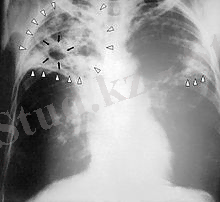

Рентгендік тексеру қатаң түрде көрсетіндімен жасалынуы керек, оның көлемі қойылған шешімге және патологиялық процесс көлеміне қарай анықталады. Бұл жағдайда сәулелі жүктеменің көлемін науқасқа және мед. қызметкерінің неғұрлым аз алуы үшін қауіпсіздік шараларын қабылдау қажет. Түзу проекциядағы рентгенографияны кейде қырынан алынған проекциямен тоықтыру керек. Бұл кезде патологиялық прцесті білудің мүмкіндігі кеңейеді. Соңғының бөліктер мен сегменттерге арақатынасын, ұзақтығын, плевра қабықтарымен және өкпе түбірі мен көкірек байланысы топографиясын анықтау. Кейбір жағдайларда рентгенографияны бейненің тура үлкейтуімен түсіру керек болады. Бұл кезде үлкейту коэффициенті 1, 5 тен аспау керек. Жоғары коэффициентте бейненің нақтылығы бұзылып, ақпарат алу мүмкіндігі азаяды. Арнайы маманданған процестерде өкпенің ұлғайтылған рентгенограммасында перибронхиалдық өзгерістердің ұзақтығы мен барлығы, жекелей алғанда дренажды бронх қабырғаларының және оларға жақын орналасқан тамырлар мен бронхтардың анықтайды. Ошақтың құрылымы талданып, кальцинаттар, қабаттар, каверналар, туберкулемдер, өкпе ұлпасындағы қосымша өзгерістер, буллезді эмфизема аумағы, плевра қабықтарының процеске енуі нақты анықталады.